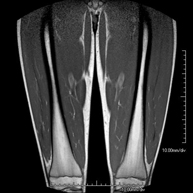

- RM Muslo

Exploración ideal para el estudio de lesiones en músculos isquiotibiales y cuadriceps, frecuentemente lesionados en deportistas. También permite una buena valoración de tendones y nervios periféricos. Tiene una duración aproximada de 20 minutos. No emplea radiación ionizante.